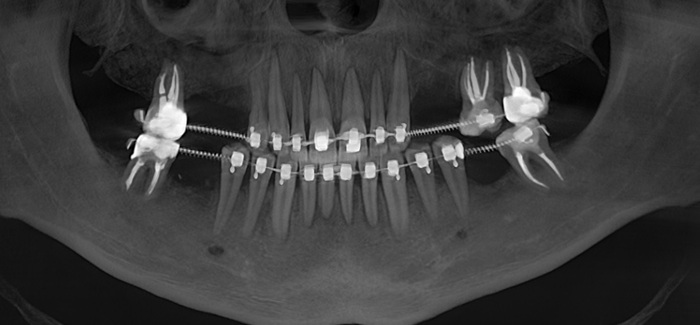

На панорамном снимке, сделанном после имплантации, хорошо видно, насколько высоко и неудачно она располагается:

Вжух и год позади:

В целом, каких-то явных изменений нет. В подтверждение тому, что это не один и тот же снимок, вы можете обратить внимание, что на имплантате уже установлена постоянная коронка.

Добрый вечер… А что это значит?... Прекрасно видно, что фолликулярная киста начала расти и оттеснять зуб мудрости дальше в пазуху, что несколько затрудняет его удаление. Блять, подумал я, надо было сразу удалять.

Контрольный снимок после удаления: